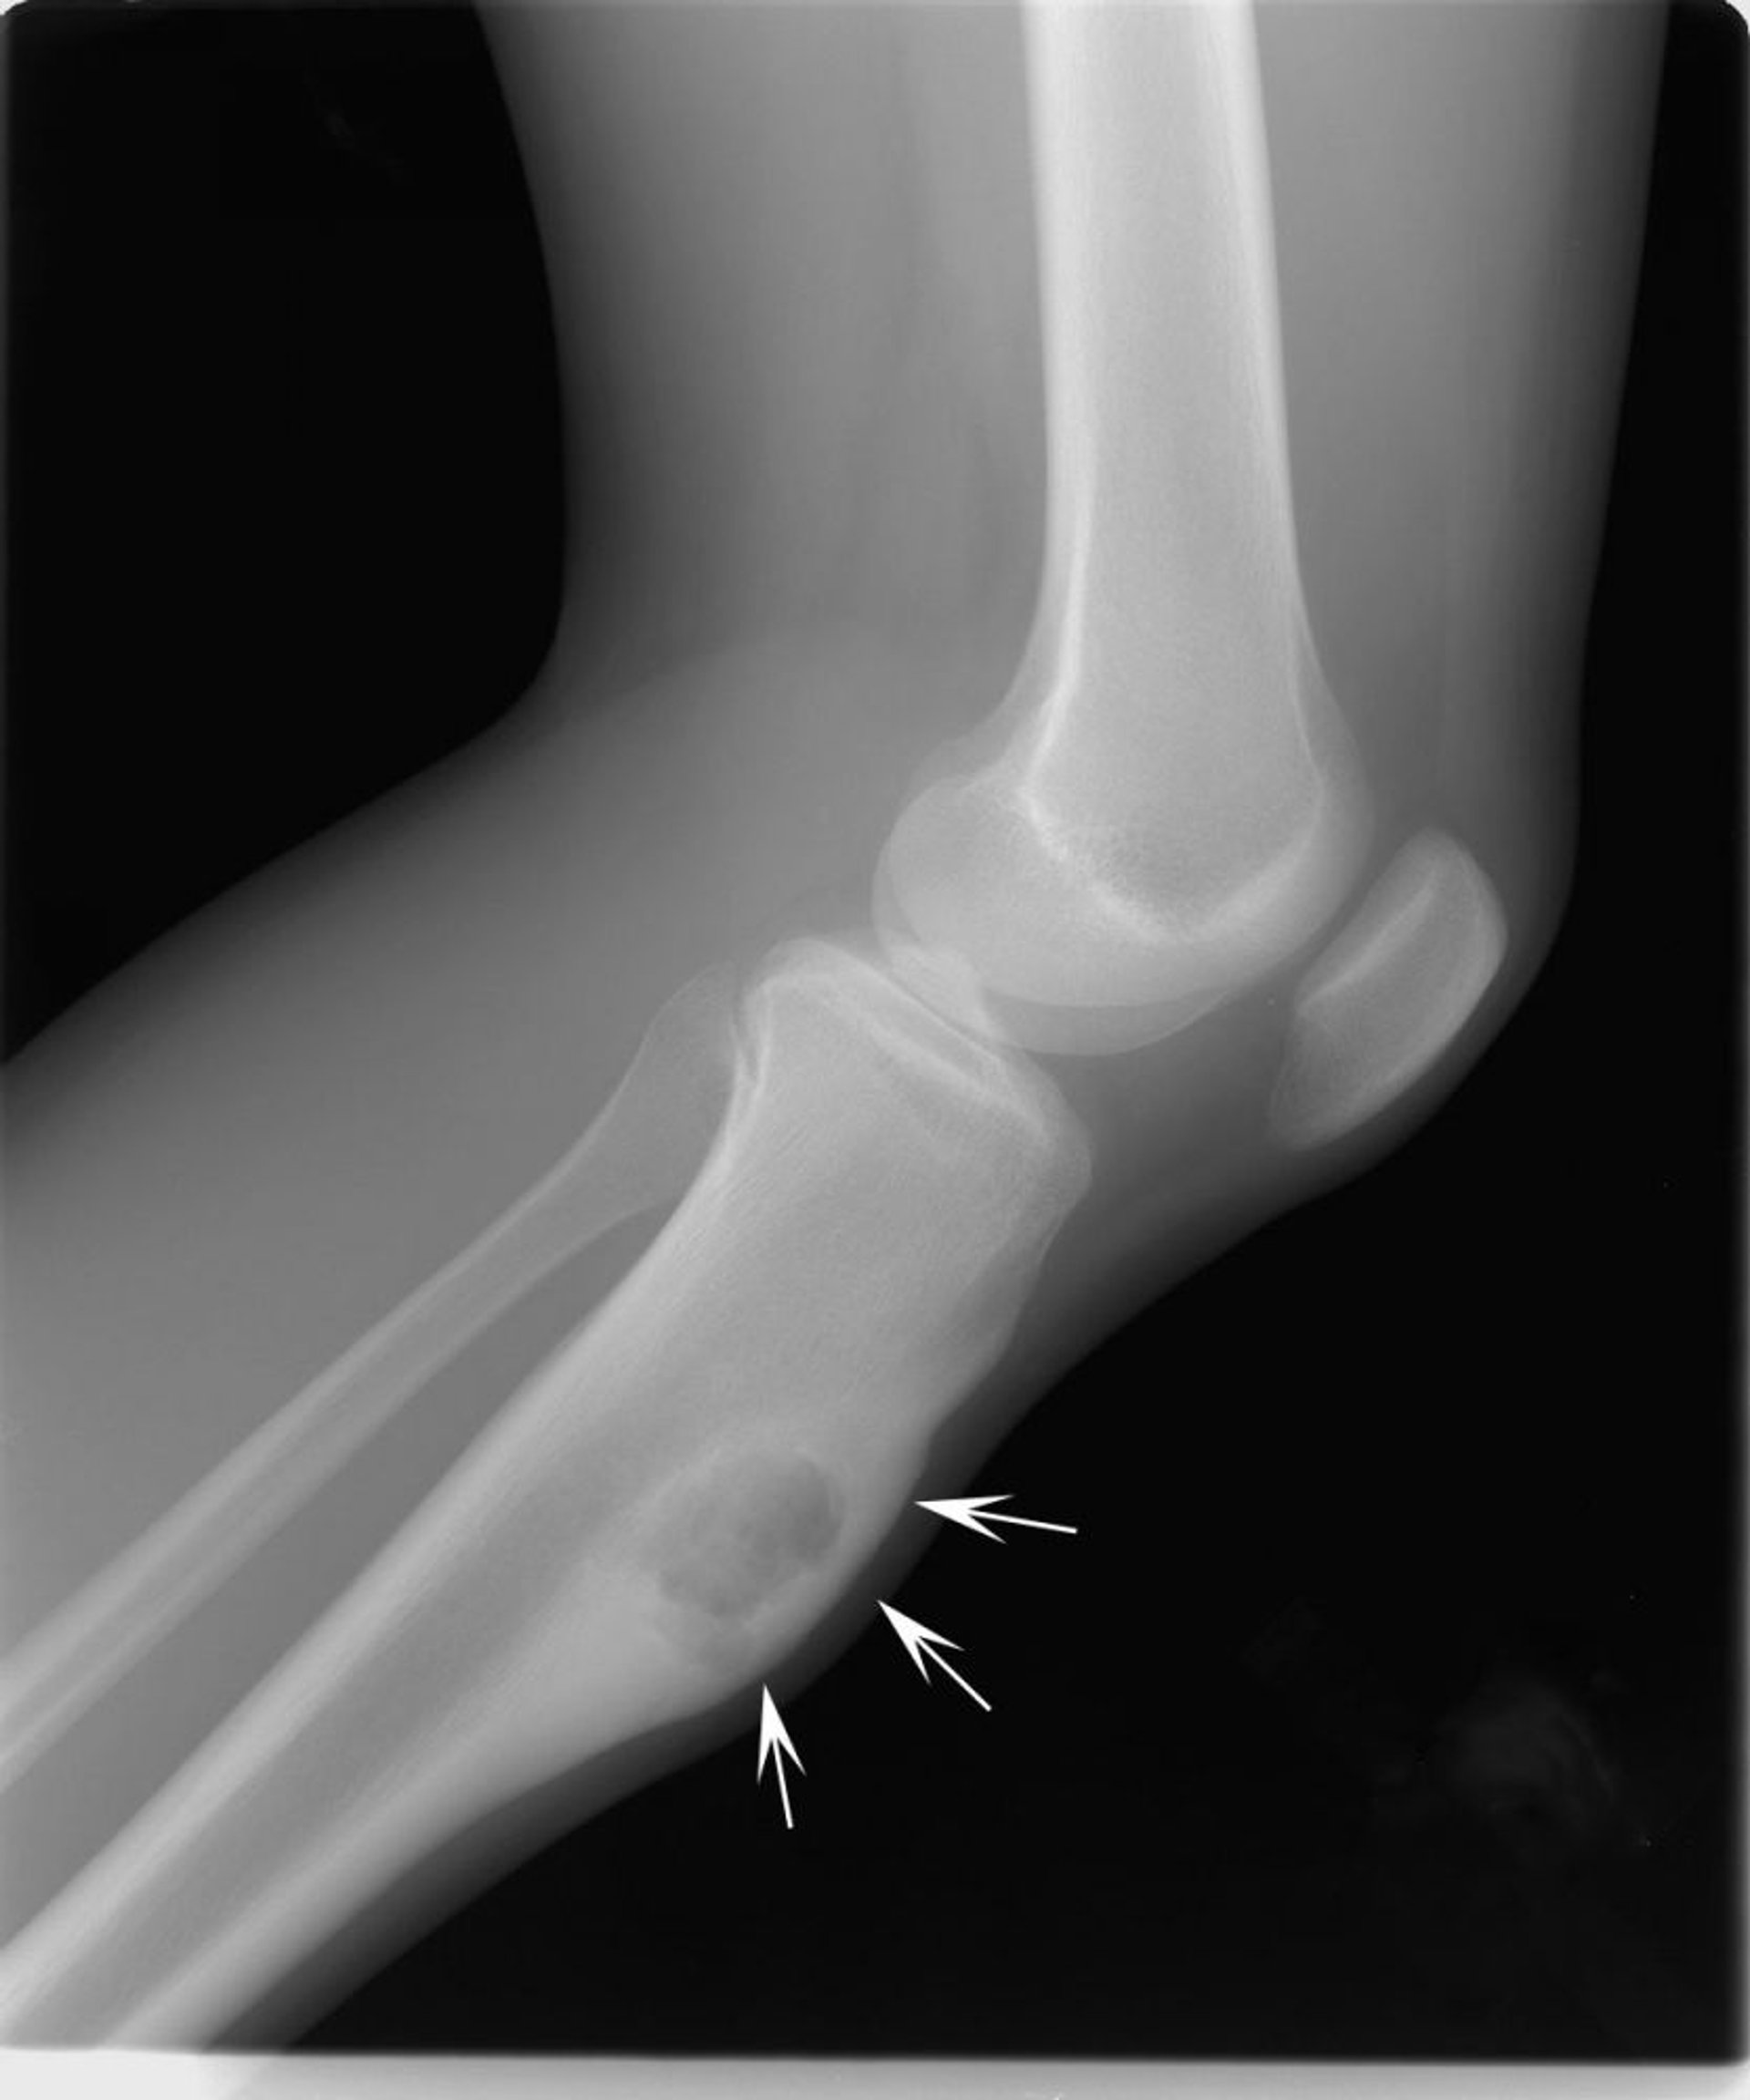

घुटने का यह एक्स-रे पिंडली की हड्डी (शिन बोन) में कॉन्ड्रोमिक्सोफ़ाइब्रोमा (तीर) दिखाता है।

मिशेल जे. जॉयस, MD, और हैकन इलास्लैन MD के छवि सौजन्य से।